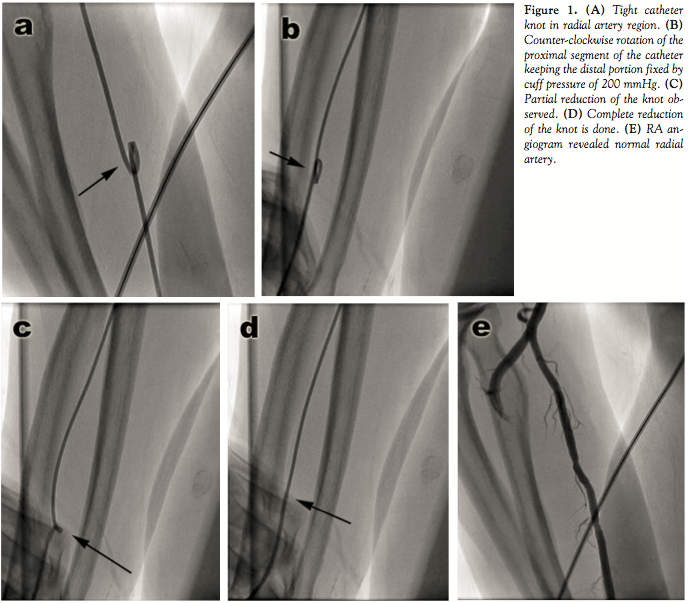

Case Report. A 75-year-old diabetic male patient with history of chronic stable angina was subjected to coronary angiography via right TRA. The ascending aorta was entered with difficulty because of significant subclavian tortuosity. Left coronary cannulation was done without difficulty using a 5 Fr Tig catheter (Terumo, Japan). However, while cannulating the RCA ostium, we encountered difficulty in catheter-tip movement despite several rotations. Suddenly, we noticed difficulty in contrast injection with simultaneous damping of pressure tracing on the monitor. Fluoroscopic examination along the catheter course revealed a tight knot of the catheter in the radial artery region (Figure 1A). We did several counter-clockwise rotations, but failed to reduce the knot. We tried to push a 0.035˝ standard guidewire through it to enlarge the knot diameter without success. We could not apply force with the guidewire because of the risk of perforating the catheter and RA. We then tried to fix the catheter distal to the knot by applying manual pressure on the brachial artery region in an attempt to reduce the knot by giving counter-clockwise rotation, but could not succeed. Because of significant subcutaneous fat in the cubital fossa, the catheter portion distal to the knot could not be fixed adequately, and while rotating the proximal end, the distal end also rotated counter-clockwise. Lastly, we applied the sphygmomanometer cuff in the brachial region and raised the cuff pressure up to 200 mmHg and successfully fixed the catheter distal to the knot. We could reduce the knot by giving several counter-clockwise rotations to the proximal portion (Figures 1B and 1C). We deflated the pressure cuff and removed the catheter. RA angiogram revealed no injury and normal radial artery (Figure 1D).

Tanner et al described a knot reduction by fixing the catheter distal to the knot using the W grabber device from the contralateral femoral route.1 Once the catheter was fixed in the segment distal to the knot, simple counter-clockwise rotation from outside was sufficient to unravel the knot. They reported a series of five cases and showed that fixing a knotted catheter distally obviated the need for passing the guidewire through the knot or passing another catheter through the loop. After unsuccessful initial attempts of counter-clockwise rotations and use of a guidewire to reduce the knot, we tried to fix the catheter distal to the knot by applying manual pressure over the brachial artery in the cubital region and attempted counter-clockwise rotation. We were unsuccessful because of inadequate fixation of the catheter segment distal to the knot due to fat in the cubital region. We then decided to apply the cuff of a sphygmomanometer in the brachial region and raised the cuff pressure up to 200 mmHg, which fixed the catheter segment distal to the knot and we could easily unknot the catheter by applying several counter-clockwise rotations under fluoroscopic guidance. This simple technique is easy to reproduce and also obviates the need for complex instrumentation as well as surgical intervention in the small-caliber RA.